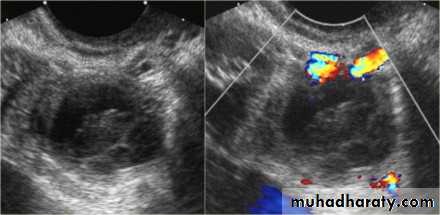

Ovarian cysts

Ovarian cysts are commonly encountered in gynecological imaging, and vary widely in etiology, from physiologic, to complex benign, to neoplastic.

Small cystic ovarian structures should be considered normal ovarian follicles unless the patient is pre-pubertal, post-menopausal, pregnant, or the mean diameter is >3.0 cm

Radiographic features

Ultrasound is usually the first imaging modality for assessment of ovarian lesions. Simple ovarian follicular cysts are:

anechoic

intraovarian or exophytic;

have an imperceptible wall